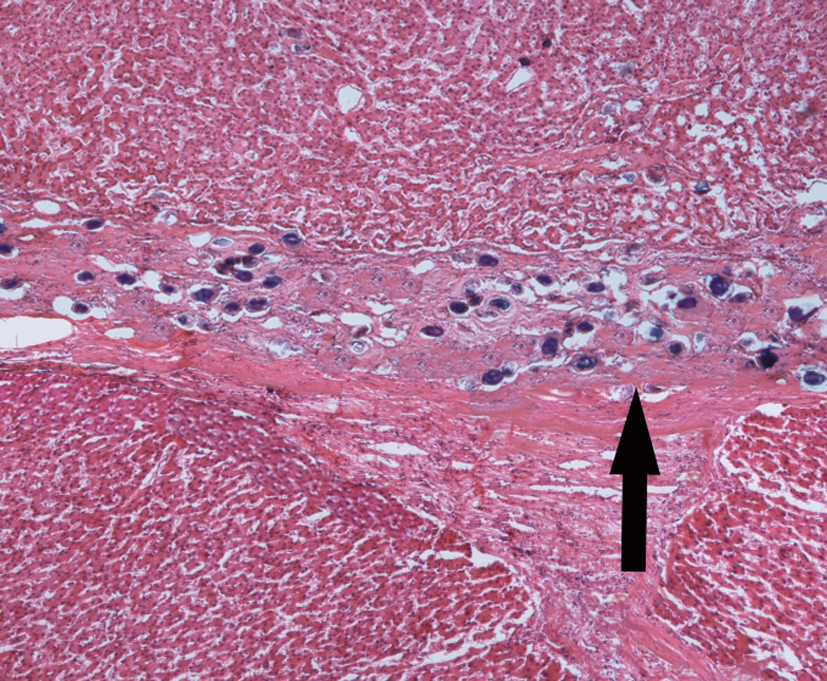

4.血吸虫性肝纤维化